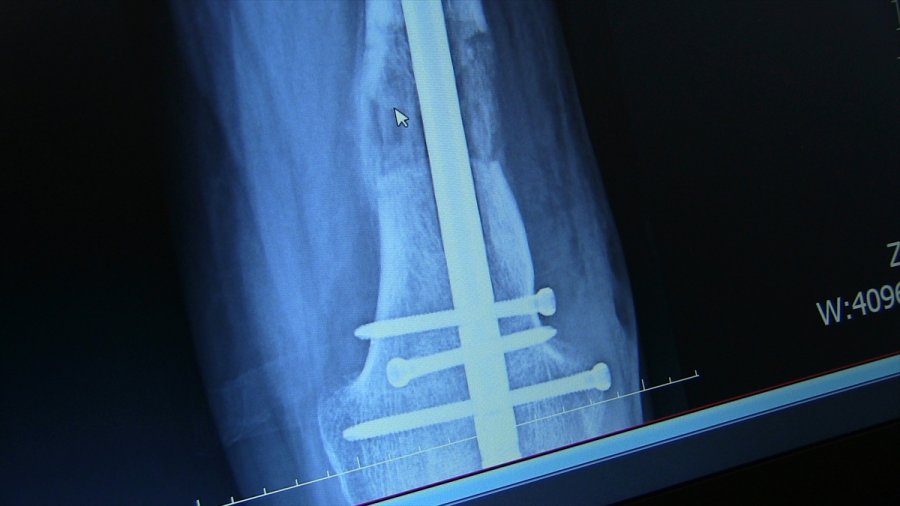

- Platin ve çivilerle ayağındaki kısalık giderildi

Hastanın yaşı ilerledikçe yürüme probleminin arttığını, sol ayağının sadece ayak parmaklarını yere basabildiğini dile getiren Arazi, "Hastamızın, ardışık ameliyatlarla bacağındaki kemikleri uzatabilme, dizindeki ve ayağındaki problemleri giderme kararı aldık. Yaptığımız ameliyatla ilk olarak bacağındaki şekil bozukluğunu düzelttik. Ardından tıbbi olarak kullandığımız çivi ve platinlerle dizin üstündeki ve dizin altındaki kemiği uzattık. Ardından topuk ve ayak bileğindeki bozukluk için de bir operasyon yaptık. Şu anda sağlığı iyi durumda." diye konuştu.